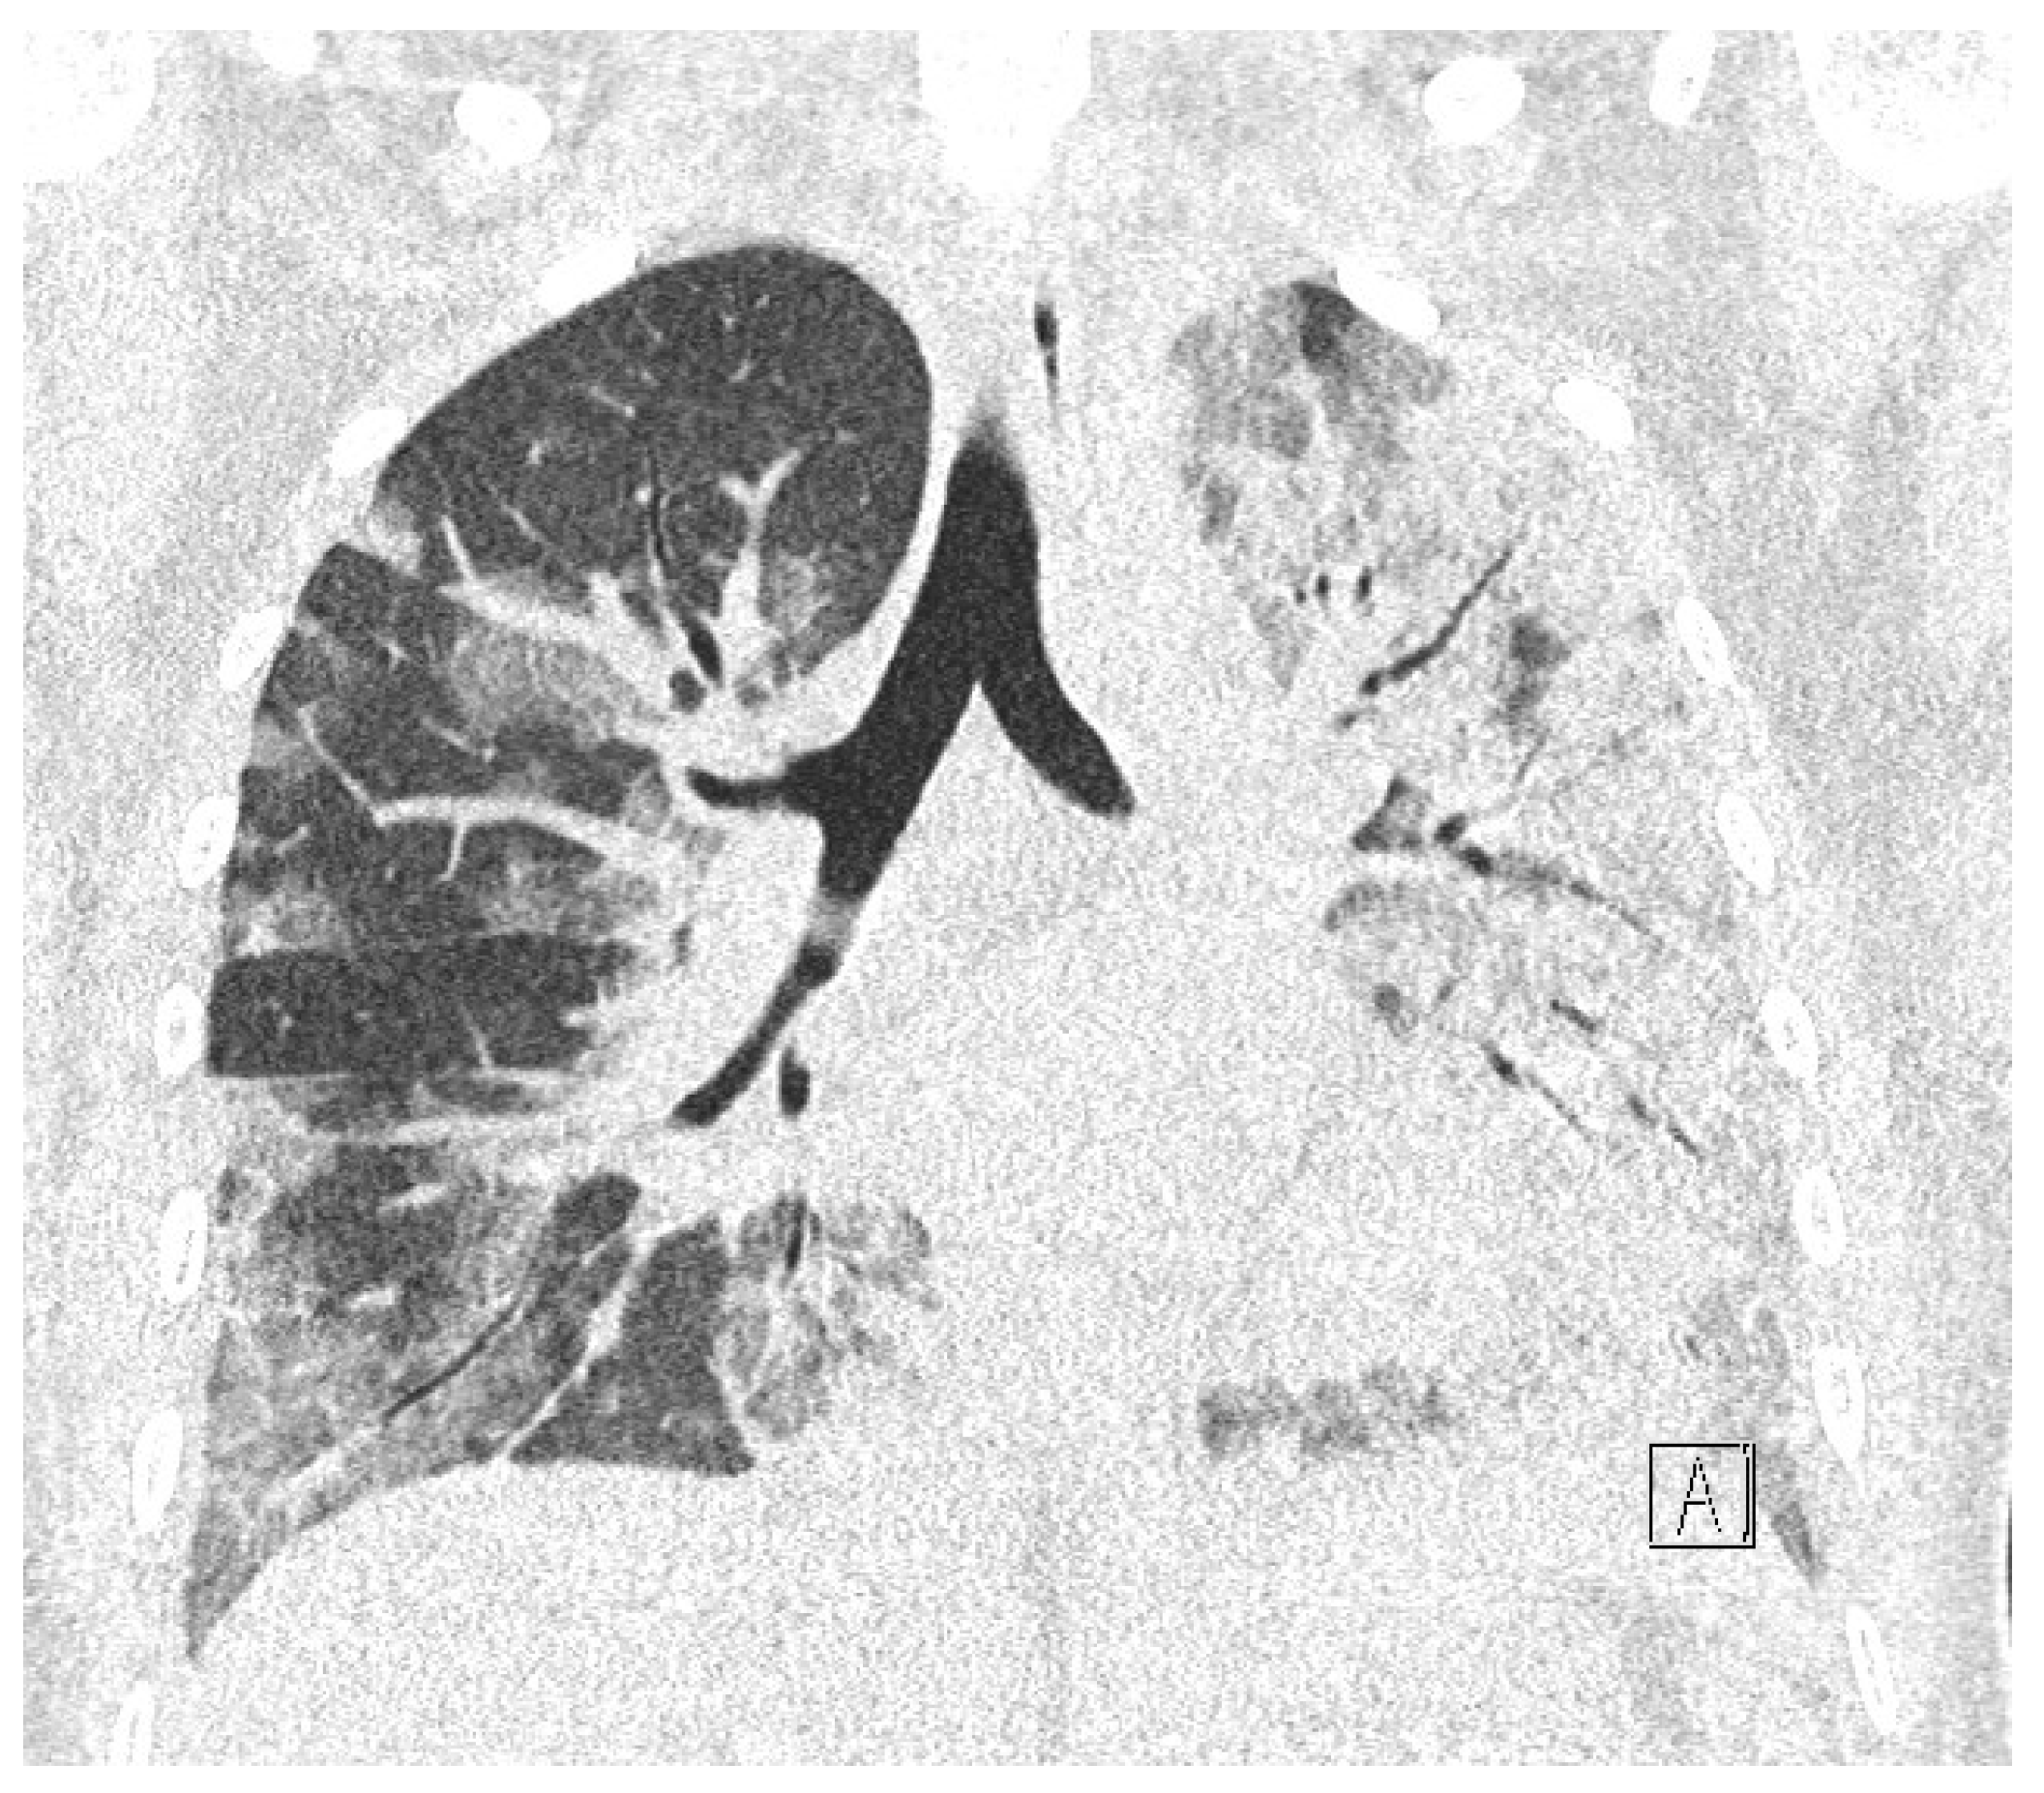

While waiting for the results of laboratory tests, a control cardiotocographic (CTG) recording was made. During the CTG recording, the foetal heart rate was found between 140 and 160 bpm. Within approximately 25 min of recording, reduced short-term variability with single decelerations and no acceleration was found—a pathological record that may suggest foetal hypoxia (Figure 1).

Figure 1.

Cardiotocography recording in a patient 1—normal baseline, reduced variability.